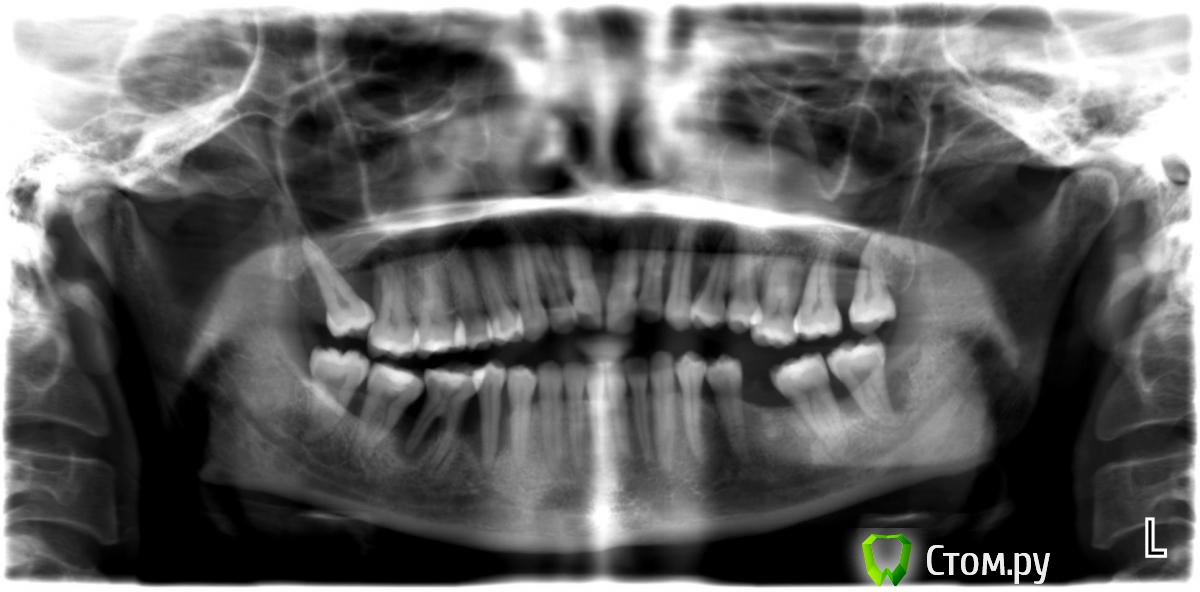

Daria1981 Опубликовано 28 августа, 2014 Поделиться Опубликовано 28 августа, 2014 Здравствуйте! Посмотрите, пожалуйста, мой снимок. Мне в клинике не дали пленку, у них все на компьютере, прислали вот такой файл. Какие зубы еще можно спасти и сколько имплантов придется поставить?Заранее большое спасибо за ответ. Ссылка на комментарий

faity Опубликовано 28 августа, 2014 Поделиться Опубликовано 28 августа, 2014 1.8, 2.8, 3.8, 4.5, 4.6, 4.8 под снос3.6, 4.5, 4.6 импланты Ссылка на комментарий

Daria1981 Опубликовано 28 августа, 2014 Автор Поделиться Опубликовано 28 августа, 2014 Спасибо за быстрый ответ! А 4.7 можно оставить, почистить хорошо? Кость сможет около него нарасти? Удалять сначала с одной стороны, а потом с другой, после установки имплантов на первую сторону?Я очень напугана моим врачом, он говорит, что в верхнем ряду у меня зуба три от силы терпимые, а остальные скоро сами выпадут. И ведь регулярно у стоматологов бывала, кариеса нет, все залечено. А на последней чистке сказали, что надо обратится к пародонтологу. И он-то меня и напугал. Ваш вариант удаления и имплантации меня просто радует после этого! Ссылка на комментарий